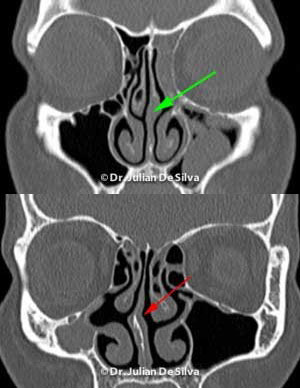

Although many patients are focused on the appearance of the nose, rhinoplasty often makes your nose smaller, breathing is important! Often a combination of straightening your septum (cartilage in the middle of nose) and graft material is required to ensure good breathing.